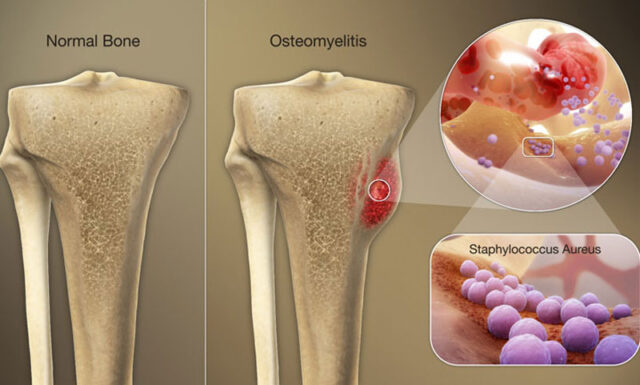

Sức khỏe của răng miệng không chỉ nằm ở men răng mà còn phụ thuộc rất nhiều vào tình trạng của xương hàm – nền móng vững chắc nâng đỡ toàn bộ hệ thống ăn nhai. Trong đó, viêm tủy xương hàm mạn tính (Chronic Osteomyelitis of the Jaw) là một bệnh lý nghiêm trọng, đặc trưng bởi tình trạng viêm kéo dài và tiến triển chậm trong mô xương hàm. Nếu không được chẩn đoán và điều trị kịp thời, bệnh có thể dẫn đến hoại tử xương, tiêu xương hàm, và gây ra những cơn đau âm ỉ dai dẳng, ảnh hưởng nặng nề đến chất lượng cuộc sống.

Viêm tủy xương hàm mạn tính là hậu quả của sự xâm nhập và tồn tại kéo dài của vi khuẩn trong mô xương. Tình trạng này khác với viêm tủy xương cấp tính ở chỗ tiến triển chậm hơn, gây tổn thương âm ỉ và dai dẳng.

Mục tiêu điều trị là tiêu diệt vi khuẩn, loại bỏ mô hoại tử và tái tạo xương khỏe mạnh.

Phẫu thuật Loại bỏ Xương hoại tử (Sequestrectomy)

- Nạo Xương Viêm (Curettage) và Loại bỏ Xương Hoại tử: Bác sĩ phẫu thuật sẽ tiến hành rạch và bóc tách niêm mạc để tiếp cận vùng xương bị viêm, sau đó nạo bỏ toàn bộ mô mềm viêm và các mảnh xương hoại tử (sequestrum). Việc loại bỏ triệt để mô bệnh lý là rất quan trọng để ngăn ngừa tái phát.